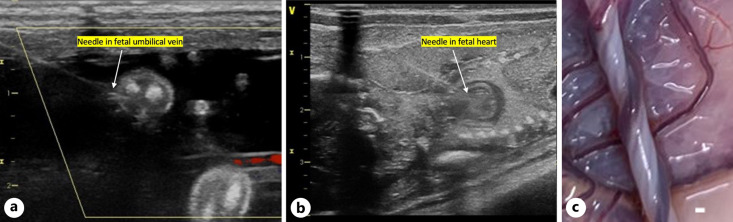

Methods: To translate this strategy clinically, the safety and efficacy of this strategy in larger animals will be necessary. We performed a pilot biodistribution study in 3 fetal nonhuman primates (NHPs) in mid-gestation examining systemic delivery of polymeric NPs loaded with fluorescent dye.